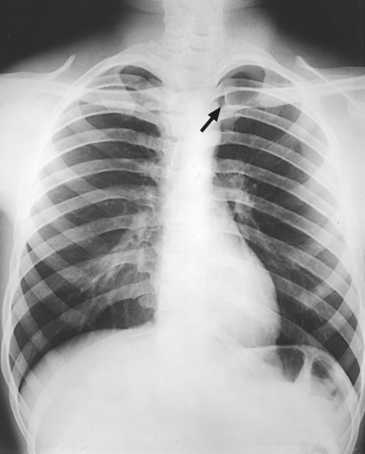

Structures shown: AP axial (Fig. 10-55) and AP axial oblique (Fig. 10-56) images of the lungs show the apices and conditions such as interlobar effusions.

Structures shown: The apices are projected above the shadows of the clavicles in the PA axial and PA projections (Fig. 10-58).